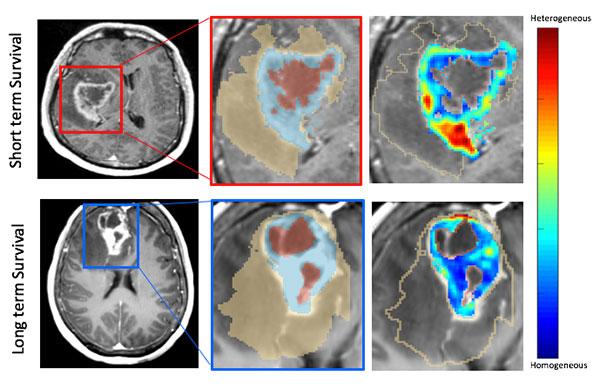

image: An example of the MRI scans showing long-term and short-term survival indications.

The AI model used by the researchers leveraged features from the region adjacent to the tumor, as well as inside the tumor to identify which patients had a poor prognosis, Pallavi said. Then, they used gene-expression information to shed light on which biological pathways were associated with those images.

"Our results demonstrated that image features associated with poor prognosis were also linked with pathways that contribute to chemo-resistance in glioblastoma. This could have huge implications in designing personalized treatment decisions in glioblastoma patients, down the road." she said.

"We can tell you who is at a better risk of survival," Beig said. "What clinicians want to do is give their patient an idea of quality of life, and since roughly 10% of these patients go on to live more than three years, that's important information."

Madabhushi said a common criticism of radiomics--drawing conclusions about tumors from the computer analysis of the images alone--is that the process is opaque and not easily interpretable.

"This is the corroborating evidence," he said. "This shows that molecular changes in the tumor are manifesting as unique representations on the scan."